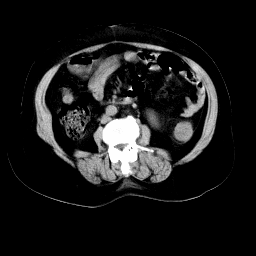

以下是引用余辉在2008-11-9 9:47:00的发言:[br]各层面均可见降结肠管壁增厚,管腔狭窄,中部层面可见管壁明显增厚区,结合病史多考虑降结肠癌,溃疡性结肠炎不除外,建议进一步检查